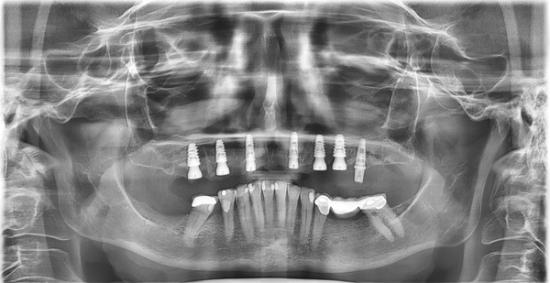

After Photo